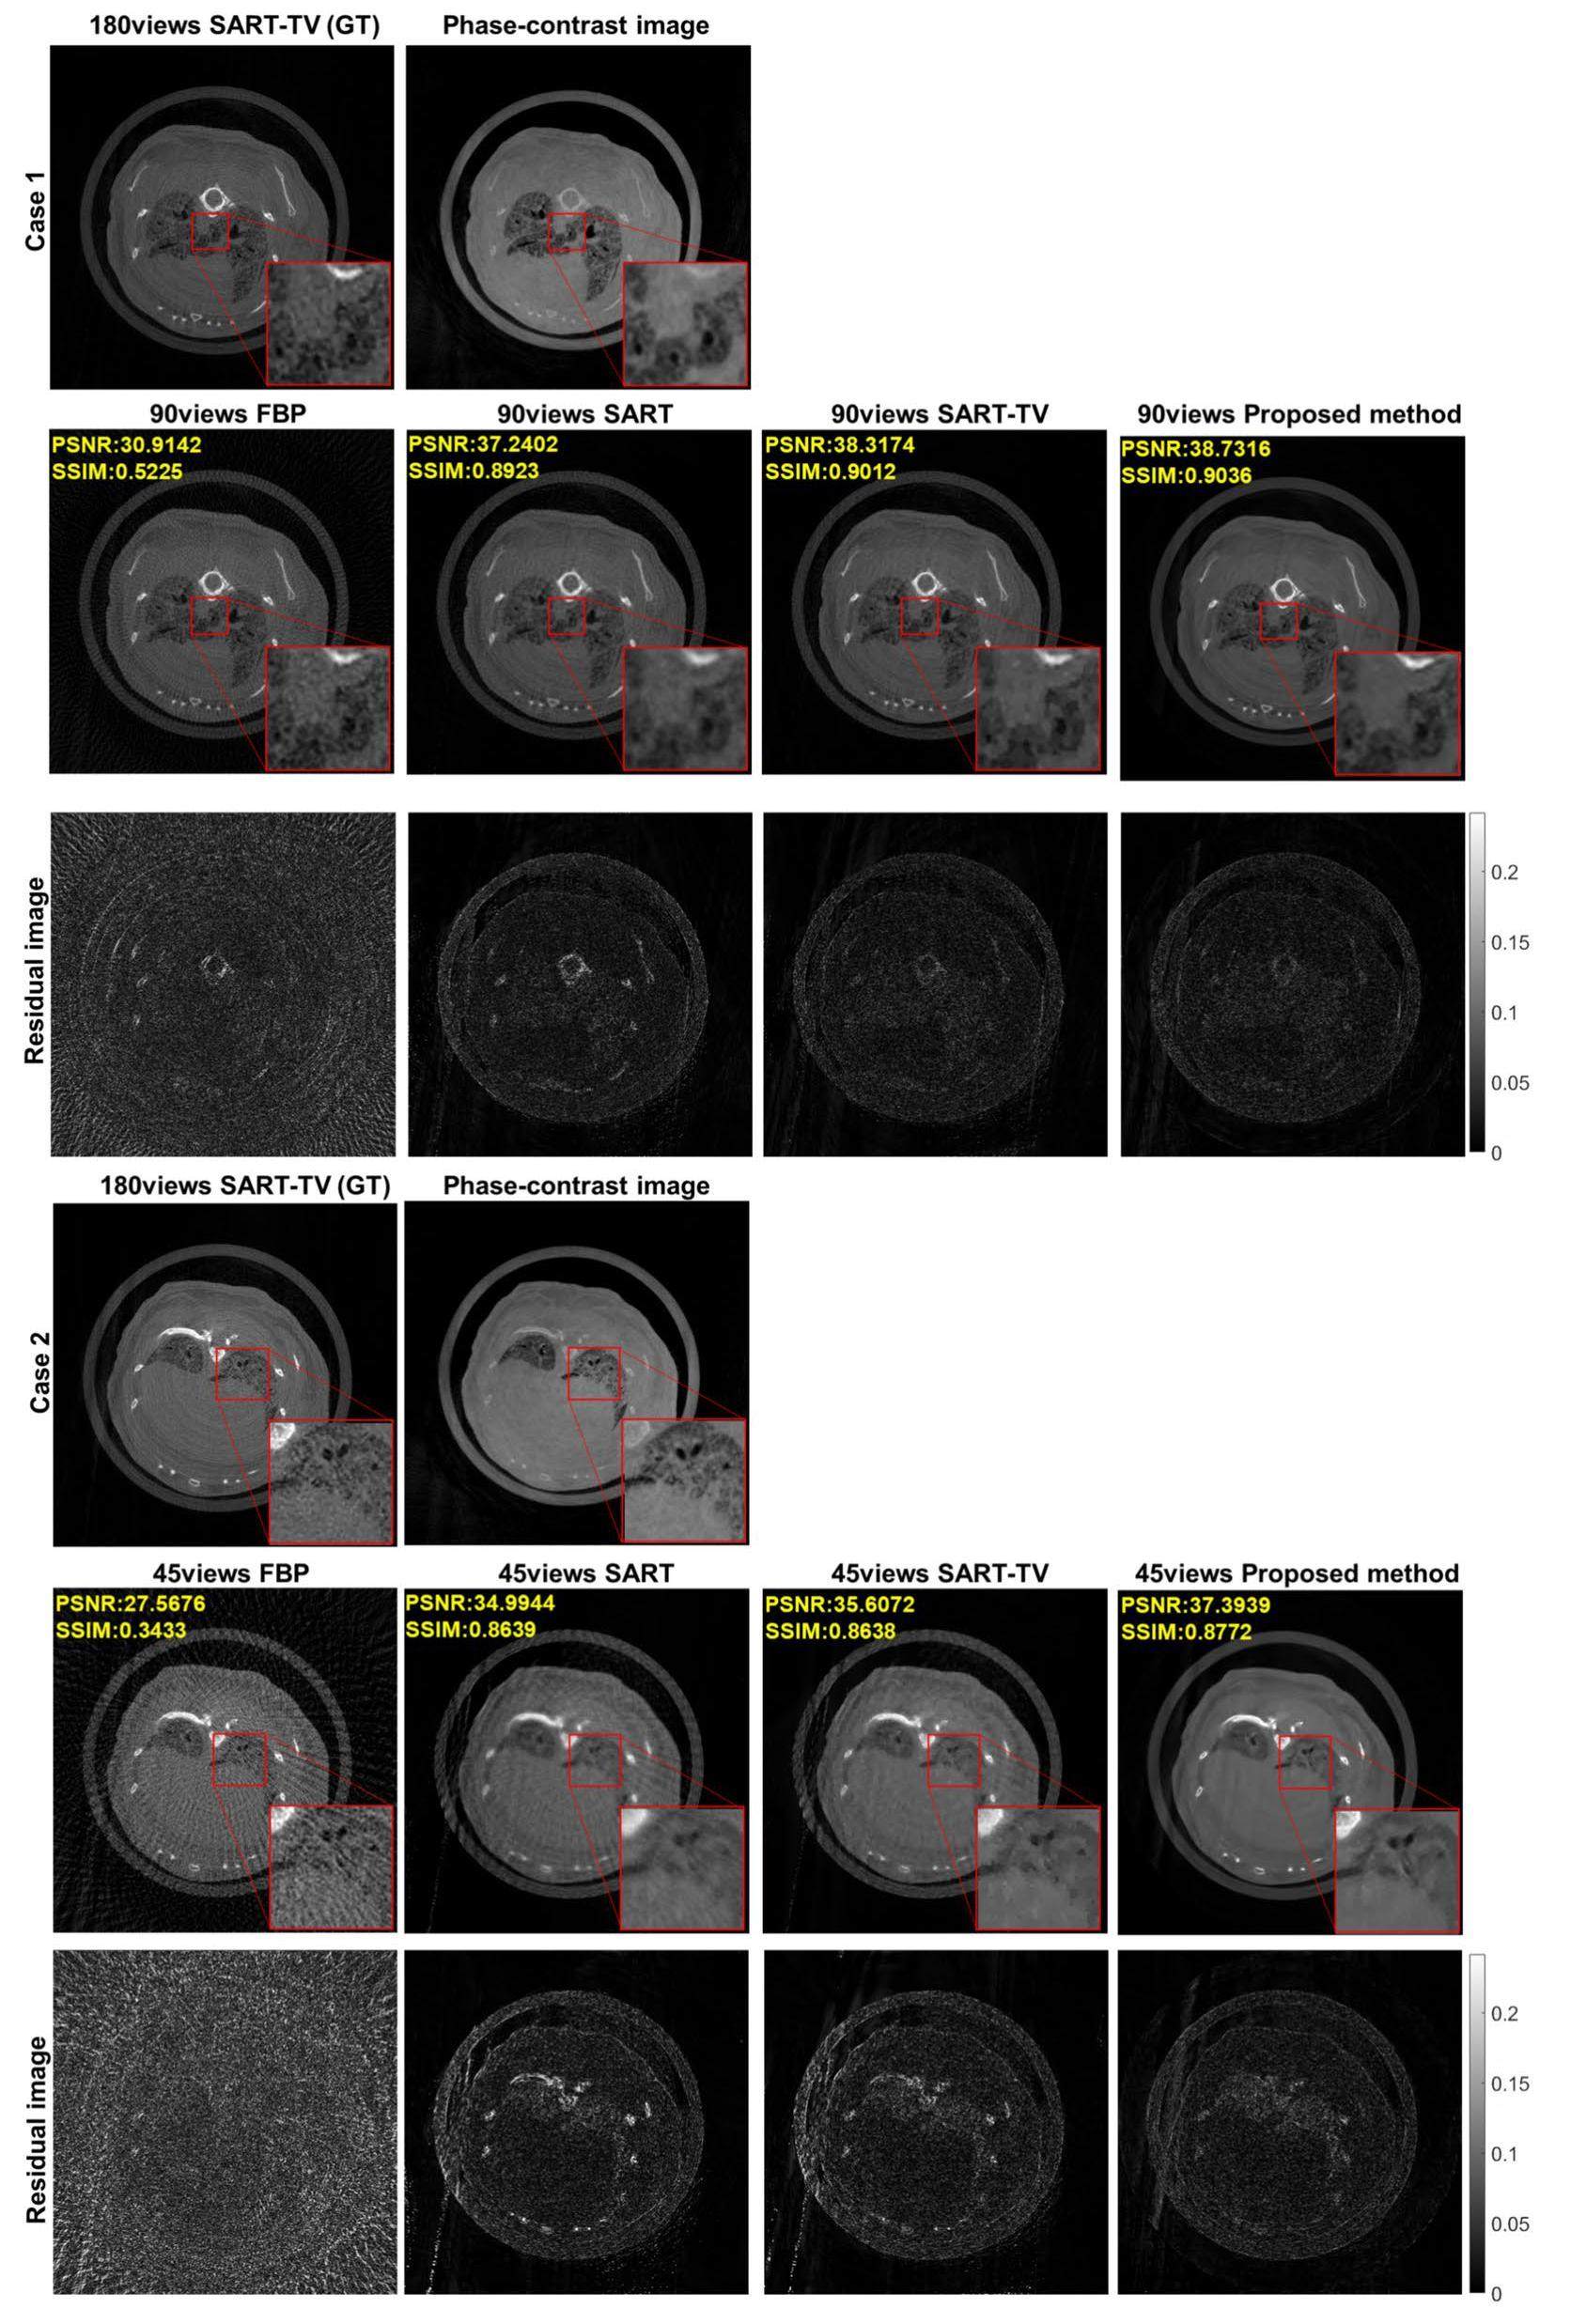

Experimental results of attenuation-based CT in phase-contrast imaging

Figure 2 illustrates the reconstructed lung slices of mice using various methods, including FBP, SART, SART-TV algorithms, and our proposed method. GT was defined as a 180-views SART-TV reconstruction. Additionally, a phase-contrast slice with enhanced contrast was included for structural comparison. These methods were employed to reconstruct slices using both 2-degree interval projections (90 views) and 4-degree interval projection (45 views) interval projections. The residual images are the error images between the reconstruction results of the different algorithms and the GT.

The FBP and SART algorithms performed poorly in both cases. In a scenario with 90 views, the SART-TV algorithm effectively suppressed stripe artifacts caused by sparse-view projections. However, noticeable smoothness and blocky artifacts were observed in the zoomed-in inner edges. When there were only 45 views, the SART-TV algorithm performed poorly, displaying excessively smooth local details and prominent streaking artifacts in the overall image. In contrast, the proposed algorithm successfully removed artifacts and maintained consistency with the GT slices in both cases. It also avoids generating blocky artifacts observed in the SART-TV algorithm. For the residual images, the proposed algorithm exhibits the smallest error. When using the phase-contrast results as references, the local zoomed-in structure is even clearer in the 90-view case using the proposed method than in the 180-view case using the SART-TV algorithm. Quantitative assessments of image quality showed that our proposed algorithm outperformed existing methods.

Experimental results of phase-contrast CT in phase-contrast imaging

Phase-contrast reconstruction of the laboratory phase-contrast CT equipment is shown in Figure 3. Currently, phase-contrast imaging algorithms rely primarily on the FBP algorithm, and we did not include a comparison with iterative algorithms. The phase-contrast projection image was calculated from the attenuation-based projection using the information separation method described in Section 2 (Methods). The GT results were reconstructed using the FBP algorithm with 180 projection views. In both the 90-view and 45 views scenarios, our proposed method outperformed the FBP algorithm in effectively removing streak artifacts caused by sparse-view projections and maintained consistency with the 180-view GT image. From the comparison of the residual images in Figure 3, the proposed method exhibits less error in the reconstruction results of the 90 views and 45 views projection data compared to the FBP algorithm. The evaluation metrics of the image quality also demonstrated the superior performance of our algorithm in reconstructing the results from sparse-view phase-contrast projections.

To validate the applicability of our method, we conducted additional calculations using the synchrotron radiation phase-contrast experimental data. Figure 3 shows the phase-contrast reconstruction obtained from the BL13W1 beamline at the Shanghai Synchrotron Radiation Facility (SSRF), China [57]. As this is a synchrotron light source, the projections are already in a parallel-beam geometry and do not require additional interpolation. The image shows a phase-contrast slice of a bee immersed in a microcentrifuge tube filled with formalin. The GT results were reconstructed using the FBP algorithm with 360-degree projection. Given the relatively simple structure of the bee, even with only 45 views, the proposed method achieved results comparable to those obtained with 360 views. The residual image comparison shows that the proposed method effectively removed the stripe artifacts.

The two sets of data presented in Figure 3 demonstrate the excellent performance of the proposed method in the field of grating-based phase-contrast imaging.